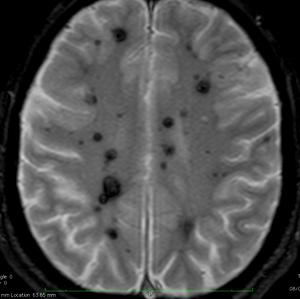

多発性海綿状血管腫 multiple cavernous hemangioma

家族性海綿状血管腫 familial cavernous hemangioma

この様な無数の海綿状血管腫を見ることがあります。多くの場合は家族性(遺伝性)の海綿状血管腫です。200個を超える海綿状血管腫があっても普通に何の障害もなく暮らしている患者さんもいます。脊髄の中にも発生しますから,脊髄のMRIもしていただきましょう。

小さな多発性の海綿状血管腫は,T2*(ティーツースター)という左の画像では見えるのですが,右にあるような普通のT1強調画像というのでははっきりみえません。

家族性多発性海綿状血管腫の患者さんは,小さな出血など生じても安易に手術を受けないようにしましょう。どの血管腫が大きくなるのかは全く予想できませんし,とても多数回の手術を受ける結果になるかもしれないからです。